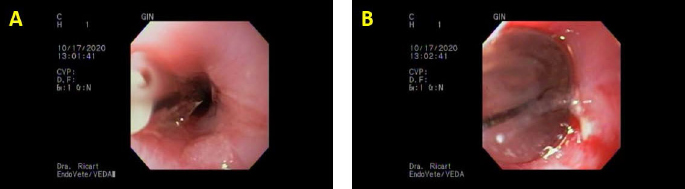

Fig. 1. The first set of dilatations with our endoscopy service. (A) Initial dilatation with a Boston Scientific CRE balloon of 12 mm. (B) Maximum inflation of the same balloon; note the mild bleeding and tearing of the mucosa; last dilatation of that day.